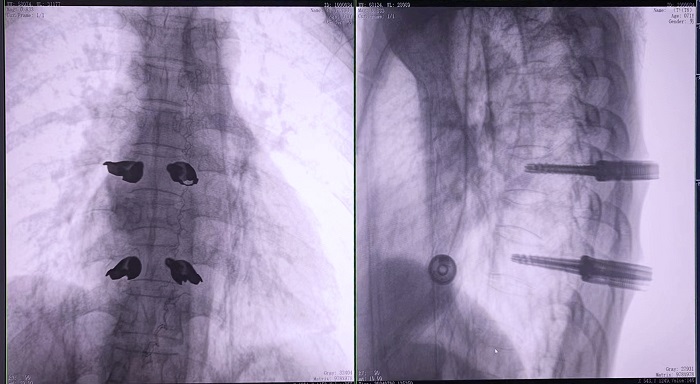

③机器人辅助胸椎手术操作难点之精准置钉

传统开放手术中,胸椎的手术视野相对受限,螺钉的置入主要依赖于医生的经验和手感,存在一定的主观性。

普爱医疗手术导航定位系统解决方案

普爱医疗骨科手术机器人的高精度机械臂,按照规划好的路径及角度,自动精准定位穿刺点,医生打入克氏针后,正侧位图像显示精度满足预期,医生完成置钉等后续手术操作。